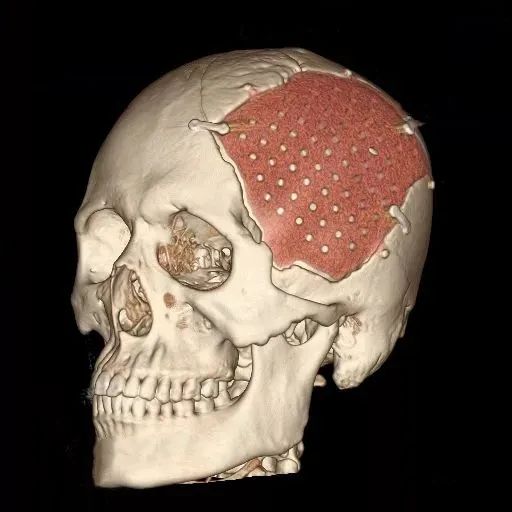

聚醚醚酮(PEEK)具有良好的加工性,因此在制造等多領域中被廣泛使用。在高溫下良好的可塑性,使得它可以通過多種加工方法進行成型,包括注塑成型、擠出、壓縮成型和旋轉成型。同時還可以通過3D技術來進行制造,這為制造各種復雜形狀和定制化產(chǎn)品提供了便利。

因此,以PEEK為材料的顱骨修補產(chǎn)品可以針對患者的缺損形狀,通過設計加工,實現(xiàn)修補產(chǎn)品與缺損的完美“嵌合”,實現(xiàn)傳統(tǒng)材料難以完成的復雜顱頜面輪廓復原。

顱骨修補術后復查

張大哥在使用了邁普醫(yī)學的PEEK顱骨修補產(chǎn)品賽盧?做完顱骨修補術后,復查結果滿意,工作和生活也都逐漸回歸了正軌!

邁普醫(yī)學采用新型材料PEEK(聚醚醚酮)開發(fā)的賽盧?顱頜面修補系統(tǒng),是基于患者CT數(shù)據(jù)個體化定制的產(chǎn)品,能精確復原顱頜面骨的輪廓外形,美學修復效果好。